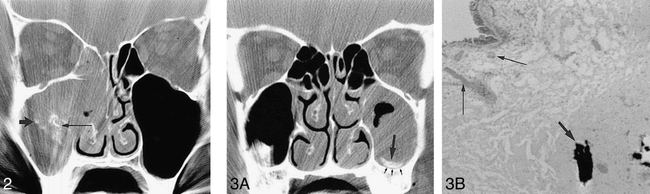

fig 3. Calcification in nonfungal sinusitis.

A, Smoothly marginated linear calcification (large arrow) is seen near the floor of the left maxillary sinus. The calcification is located at the periphery of the sinus and there is a thin layer of soft-tissue density (small arrows) separating the calcification from the sinus wall.

B, Photomicrograph of surgical specimen shows calcification (short arrow) within the thickened fibrotic submucosal layer of the maxillary sinus. Vascular congestion with dilated capillaries (long arrows) is seen in the edematous superficial submucosal layer (hematoxylin-eosin, original magnification ×100).